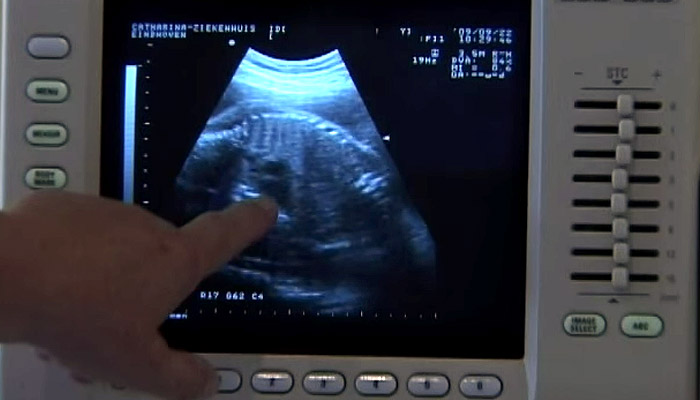

In het Catharina Ziekenhuis worden per jaar ruim 300 baby’s geboren door middel van een keizersnede. De voorlichtingsfilm over een keizersnede geeft een heel duidelijk beeld van deze ingreep. Ook ziet u hoe wij huid-op-huid contact toepassen. Het kindje wordt direct na de geboorte bij de moeder op de borst gelegd. Voor de binding tussen ouders en kind is het heel belangrijk dat ze meteen na de geboorte bij elkaar zijn. Uit onderzoek blijkt dat het ook voor de borstvoeding belangrijk is. Huid-op-huid contact na een keizersnede is niet heel vanzelfsprekend. Het wordt op dit moment in een beperkt aantal ziekenhuizen in de Benelux aangeboden. Heeft u na het zien van de film vragen, neem contact op met uw arts of met polikliniek Gynaecologie via telefoonnummer 040 – 239 93 00.

Voorlichtingsvideo over een keizersnede